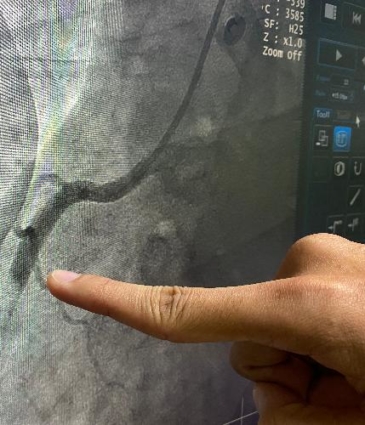

When you visit Dr Sayan Sen, he’ll listen carefully to your symptoms, lifestyle, and medical history. He may recommend investigations such as an ECG, echocardiogram, or coronary angiography to assess your heart’s structure and blood flow.

For exercise-related chest pain, treadmill or stress echocardiogram tests help evaluate how your heart responds to exertion. If breathlessness or palpitations accompany your chest pain, additional monitoring such as a Holter monitor may be advised. Dr Sen tailors investigations based on each patient’s needs, aiming to provide clear answers. If a heart condition is identified, he will offer treatment options such as medication, lifestyle advice, or further specialist intervention – always delivered with personalised, trusted care.

Angiography

Angioplasty (Stent)